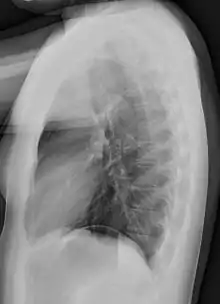

Chest X-ray PA inverted and enhanced.